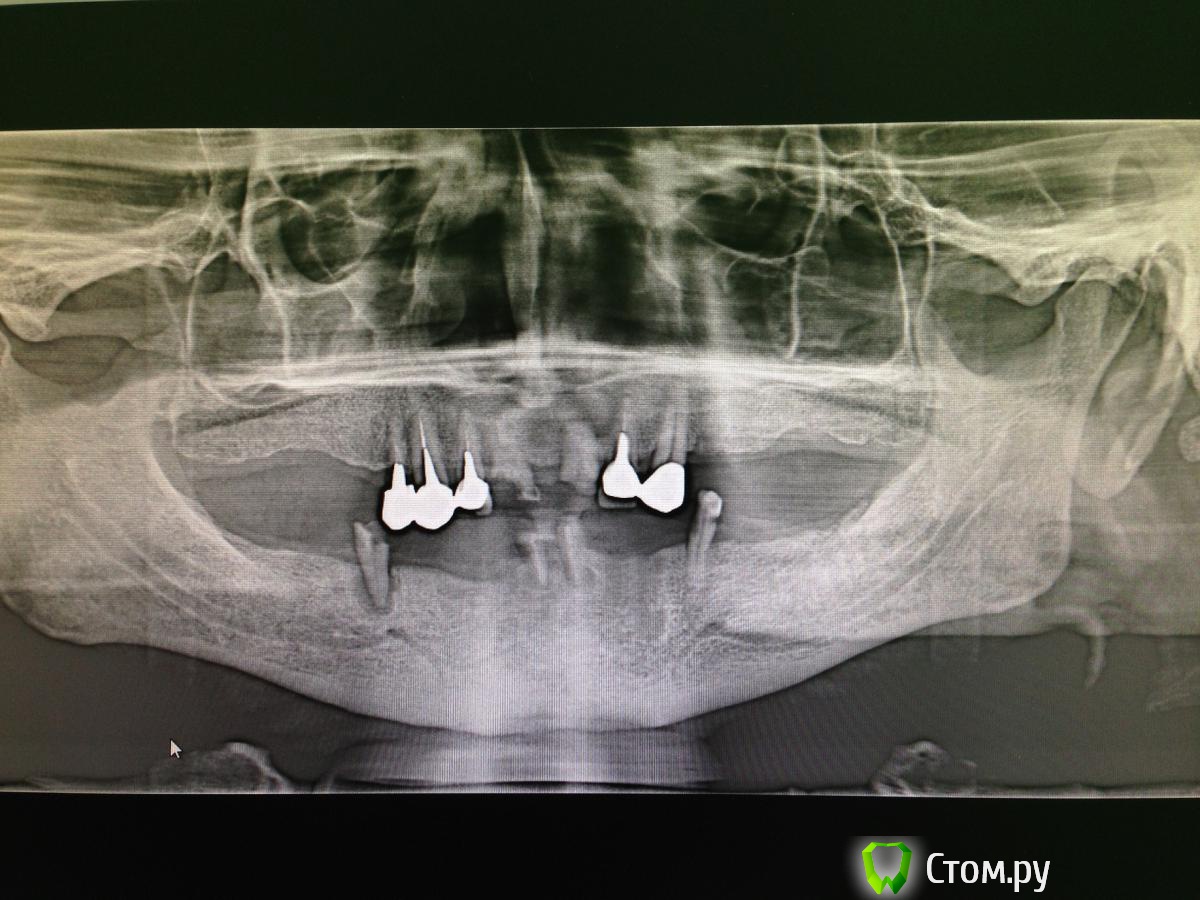

diesel87 Опубликовано 14 февраля, 2014 Поделиться Опубликовано 14 февраля, 2014 Добрый вечер коллеги, планируется частично-съемный протез на нижнюю челюсть, балочная система, интересует позиция имплантатов, 35, 32, 42,45 подойдет? и еще, после операции имплантации когда можно изготовить съемник и дать пациенту в пользование чтоб он начинал к нему привыкать пока без фиксации на балке и имплантатах, с не большими углублениями в зоне имплантатов, чтоб не было на них ранней назрузки? нижние зубы удалены 2 месяца назад Ссылка на комментарий

kriokov Опубликовано 15 февраля, 2014 Поделиться Опубликовано 15 февраля, 2014 В каталоге максимально приближенное к системе локатор нашел вот что толькоScreenshot_2014-02-15-12-50-23.pngScreenshot_2014-02-15-12-50-13.pngу дентиума, да только эти. Но это не совсем локаторы. У локаторов работает не только наружная часть втулки , но и внутренняя. Под локаторы корейцев не вкручивал. Вкручивал МИС с шестигранным индексом, у МИС локатор патентованный, не собственного изобретения. Но это ортопед решает.По позициям на нижней челюсти если получалось то 44 42 32 34. Если не получалось в этих позициях, то приходилось сдвигаться. Обратите внимание на расстояние между имплантатами, колпаки в протезе под локаторы должны не мешать друг другу.На что бы обратил внимание учитывая свои косяки-- в идеале предварительная постановка зубов с протезом на н.челюсти-- параллельность при введении имплантатов-- делал так, сначала запиливал пилотником строго по центру нижней челюсти осевой канал, в него длинный пин параллельности, смотрел осевую относительно верхней челюсти, если надо поправлял, потом уже от центра сверлил сначала дистально , потом медиально по измеренному расстоянию от осевой. Не ленитесь проверят параллельность на каждом этапе. У меня параллелометра Авраами нет, поэтому так делал.--- во фронте хорошо вниз тянет подбородочная мышца, поэтому тут шью горизонтальные матрацные, а после них либо обычные кнопочные, либо крос-крест--- обратите внимание на количество кератинизированной десны, при локаторах важно 3 Ссылка на комментарий